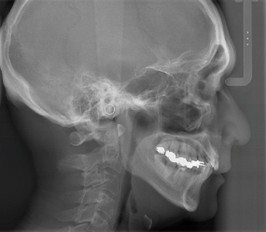

3.矯正治療に欠かせない『セファログラム』(矯正用頭部X線撮影)

セファログラム(頭部X線規格写真)は、骨格と歯の関係を詳細に分析し、適切な治療計画の立案や治療効果の客観的評価に欠かせないX線検査です。

セファログラムの種類と分析内容

セファログラムには、「側面セファログラム」と「正面セファログラム」の2種類があります。

| 側面セファログラム | 顎の前後的な関係、歯の傾斜角度、上顎と下顎の位置バランス |

セファログラムでは、X線写真に基準点を設定し、角度や距離を測定することで骨格や歯の位置関係を数値化します。

これにより、正確な診断や矯正治療の計画を立てるための重要な情報を得ることができます。

側面セファログラム